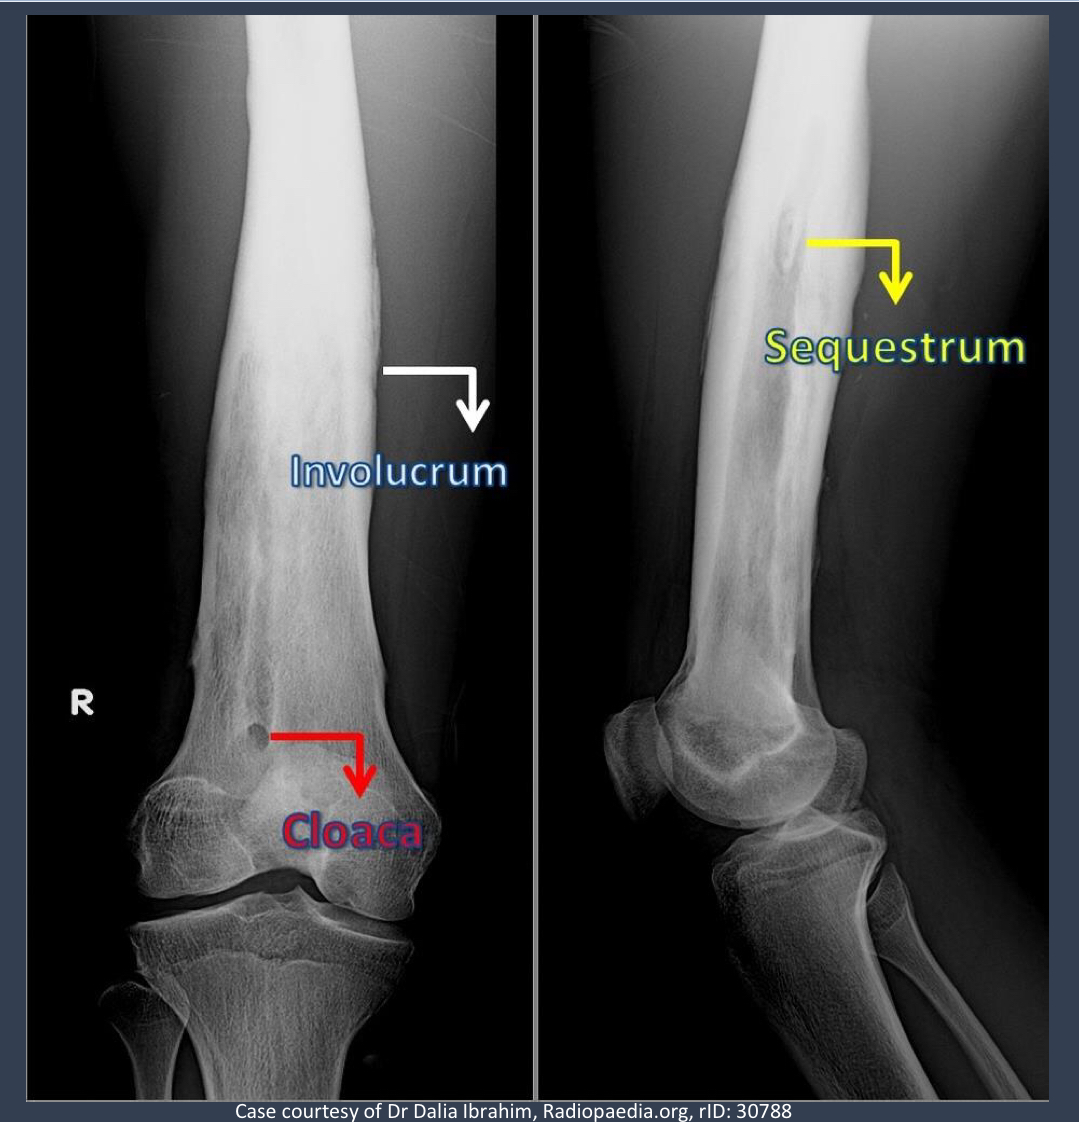

what is noteable in the long bone?

involucrum = thick layer of periosteal new bone that forms around sequestrom

what is the opening from the bone to the skin called that may show up in this patient?

cloaca = opening in an involucrum that drains pus and debris out of infected bone

via sinus tract